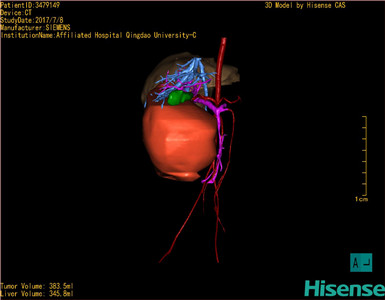

将0.625mm双源薄层CT资料的静脉期和动脉期Dicom格式文件导入海信CAS系统。

通过调节窗宽窗位调整CT序号,对肝实质,胆囊,下腔静脉,肿瘤,肝动脉、门静脉及肝静脉等进行三维重建;系统自动计算肝脏体积。

模拟手术操作,自动计算切除肿瘤体积。肝脏体积为345.8ml,肿瘤体积383.5ml,是肝脏体积的1.1倍,通过比对6-9月岁正常肝脏体积为257.75±51.05ml,通过术前模拟手术,精准判断切除后剩余肝脏体积能耐受,避免肝衰竭发生。

术前三维重建:

重建图片